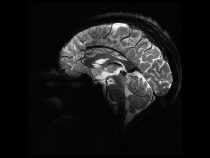

Najvýkonnejší MRI prístroj

Francúzski vedci vyvinuli MRI zariadenie vhodné pre ľudí trpiacich klaustrofóbiou, ktoré zároveň pracuje s magnetom produkujúcim rekordné magnetické pole. V posledných desaťročiach sa na diagnostické účely čoraz častejšie používajú zariadenia či prístroje pracujúce na báze zložitých fyzikálnych procesov prebiehajúcich v jadrách atómov. Jedným z takýchto… pokračuj